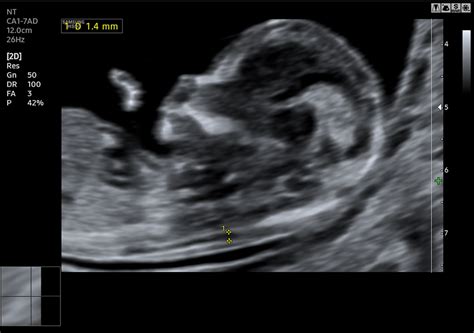

Kétféle magzati prenatális vizsgálóeljárás létezik: Nem invazív eljárások: ultrahang, anyai szérum marker vizsgálat és az anyai vér vizsgálata. Nem invazív eljárások: Ez egyik lehetőség az ultrahang és anyai szérum marker vizsgálata. Ez a vizsgálat is több módon végezhető, azonban a legelterjedtebb és a legpraktikusabb az ún. kombinált szűrőteszt, ami két részből áll: genetikai ultrahangvizsgálatból és vérvizsgálatból. A szűrővizsgálat vérvizsgálat részének keretén belül az anyai vérben található két, a méhlepény által termelt magzati plazmafehérje koncentrációjának (szabad ß-hCG és PAPP-A) meghatározása történik, melyek úgynevezett vérbiokémiai markerek. A genetikai ultrahangvizsgálatot, egyben a kombinált szűrőtesztet is 12-14.hét között kell elvégezni.

Nemzetközi adatok szerint a szív a leggyakrabban érintett szerv a magzat fejlődési rendellenességeiben, emellett a leggyakoribb kromoszóma-rendellenességek (Down-, Edwards-, Patau-szindróma) nagy százalékban szívhibával is társulnak. Átfogó magzati szűrővizsgálatot három alkalommal ajánlunk: a 12. héten, a 20. héten és a 30. héten. A vizsgálatokat az FMF (Fetal Medicine Foundation London) által képzett és regisztrált orvosok végzik, akiknek tevékenységét a szervezet évente ellenőrzi és auditálja.